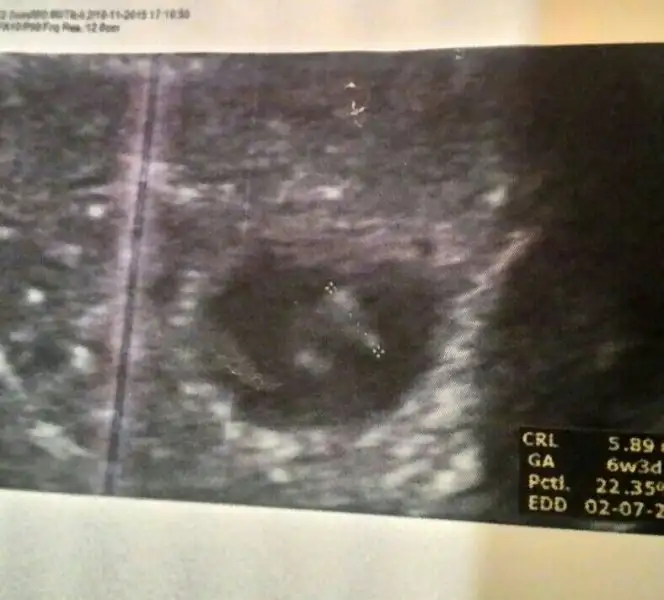

Şimdi kendi usg me tekrar baktım. 6+3 günlük karından. Tekrar bakar mısın canım.Evet canım bende okumuştum zaten bebekle plasentanın farklı yerlerde olduğunu biliyorum. Slvestr arkadaşımız bebek nerdeyse plasentada orda olur demişti. Ama öyle değil. Benim ilk gebeliğimde bariz bebek solda hatta en sola yapışık yani. Ama plasenta sağda ve benim 11 aylık bir cimcimem var. Yani plasenta olayı ilk gebeliğimde tuttu. Şimdi bebekte plasentada solda bakalım sonuç ne olacak. Eğer yine kızım olursa plasenta olayı yalan arkadaşlar. Tutanlar tesadüf dicez napalım

Canım bu vajinal ultrason ve bebek sağda, teoriye göre erkek, demek ki sen de tutmuyor..Kızlar kızımın ultrasonu buldum diğer konularda kaydetmisim,resim atiyorumm bundada plasenta solda gibi geldi bana

Eki Görüntüle 1715548